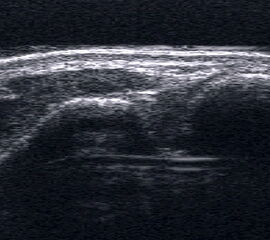

Längsschnitt über dem Lig. fibulocalcaneare. Die Peronealsehnen erscheinen als echoreiche runde bis ovaläre Struktur.

Abbildung 19

Lagerung: Rückenlage, OSG in Neutralstellung.

Schnittebene: LS über Lig. fibulocalcaneare.

Referenzstrukturen: Fibulaspitze und Talus.

Befunde: Das Lig. fibulocalcaneare is nativ schlecht abgrenzbar, da es in die Tiefe und nicht parallel zum Schallkopf verläuft. Direkt über das Band ziehen quer getroffen die Peronäussehnen. Durch die Distorsion kann auch das Peritendineum peroneale einreißen. Die Peronealsehnen sind dann in ihrer Sehnenscheide von Blut umgeben, was sich als echoarmer Ring (Halo-Phänomen) darstellt und ein indirektes Zeichen für eine Verletzung des Lig. fibulocalcaneare ist.